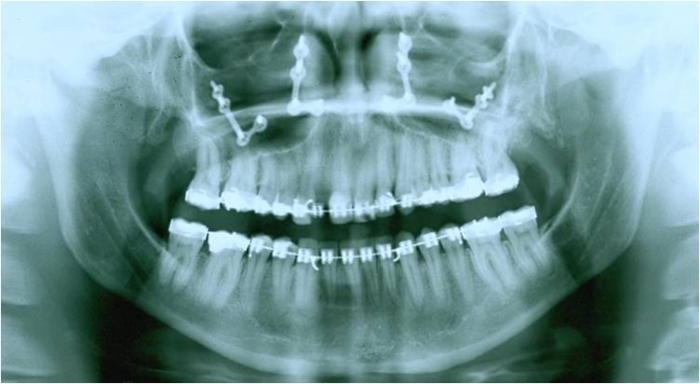

Raio X após cirurgia ortognática de avanço de maxila - Clínica Cliniface

Raio X após cirurgia ortognática de avanço de maxila